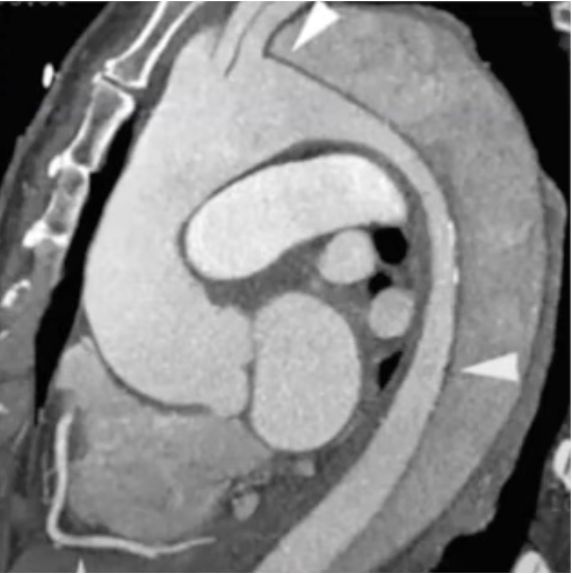

🫀💥 Answer: LAD occlusion Classic anterior wall / anteroseptal infarct pattern = LAD territory 🚨 Bonus points: proximal LAD if you’re seeing a big anterior + septal involvement. #RadTwitter #Cardiology #Radiology #MedTwitter #Radres

🫀⚡️ Unknown MI case Which coronary artery took this patient down? 👀 💥 Classic infarct pattern on imaging. 🎯 Name the culprit vessel! 👇 Drop your answer #RadTwitter #Cardiology #Radiology #MedTwitter #CCTA #Radres